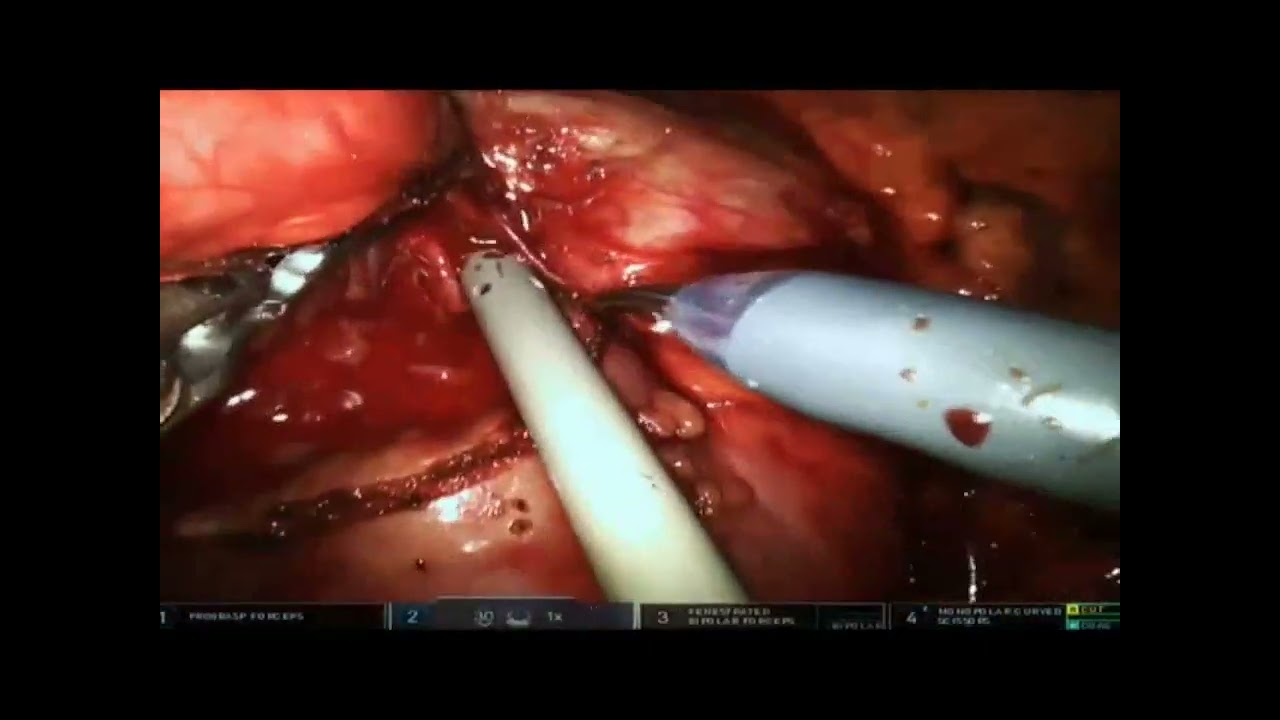

Robot-assisted radioguided surgery using a DROP-IN gamma probe